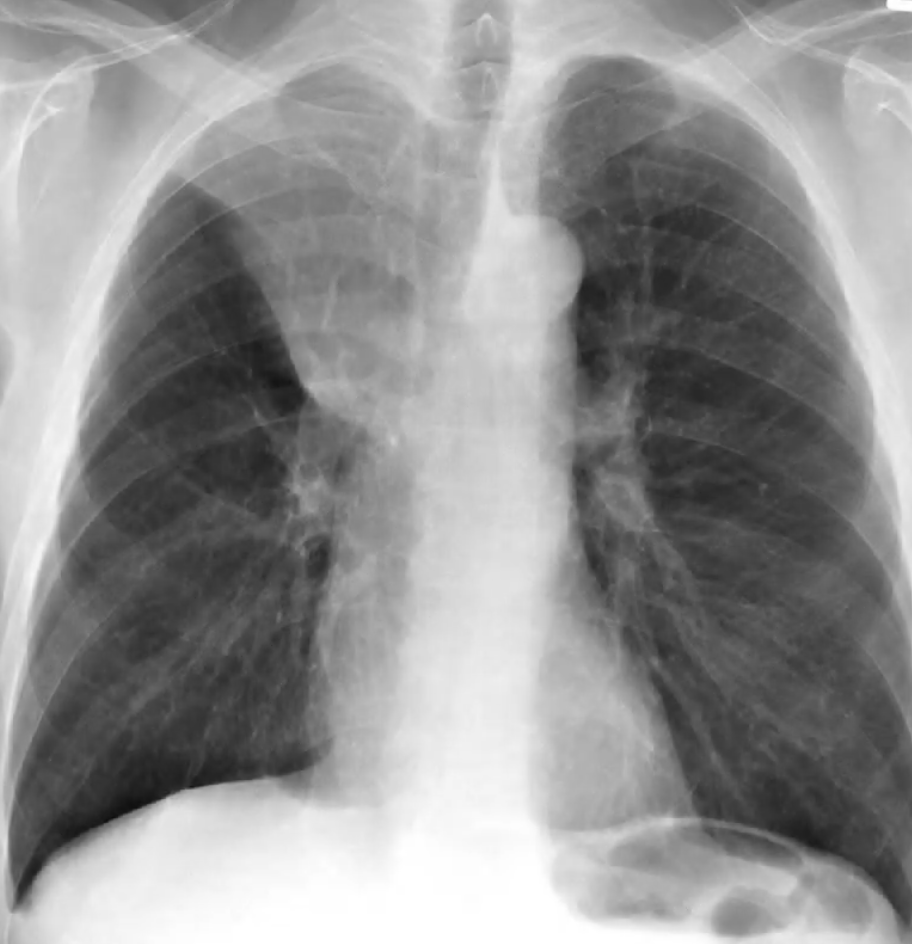

Hyperinflation

Subjective impression that total lung capacity is likely increased based upon number of ribs seen, flattening of the diaphragms, and diffusely increased lucency of the lungs. Seen in COPD and asthma only during exacerbations.

Alveolar (Airspace) Opacities

Due to fluid accumulation within the alveoli and terminal bronchioles; fluid may be oedema, pus, or blood. Opacities are hazy with poorly defined margins but can respect lobar boundaries (unless diffuse).

Differentials are divided into cardiogenic and non-cardiogenic pulmonary oedema (see Acute Pulmonary Oedema). Non-cardiogenic pulmonary oedema defines a spectrum between acute lung injury and acute respiratory distress syndrome.

Differentiation of cardiogenic and non-cardiogenic pulmonary oedema:

Kerley lines

- Kerley A lines are diagonal, unbranching lines 2–6 cm long extending from the hilum, representing channels between peripheral and central lymphatics

- Kerley B lines are faint thin horizontal lines 1–2 cm long at the lung periphery, usually at the bases, representing interlobular septa

Other features: cephalisation (upper lung diversion), bat’s wing pattern